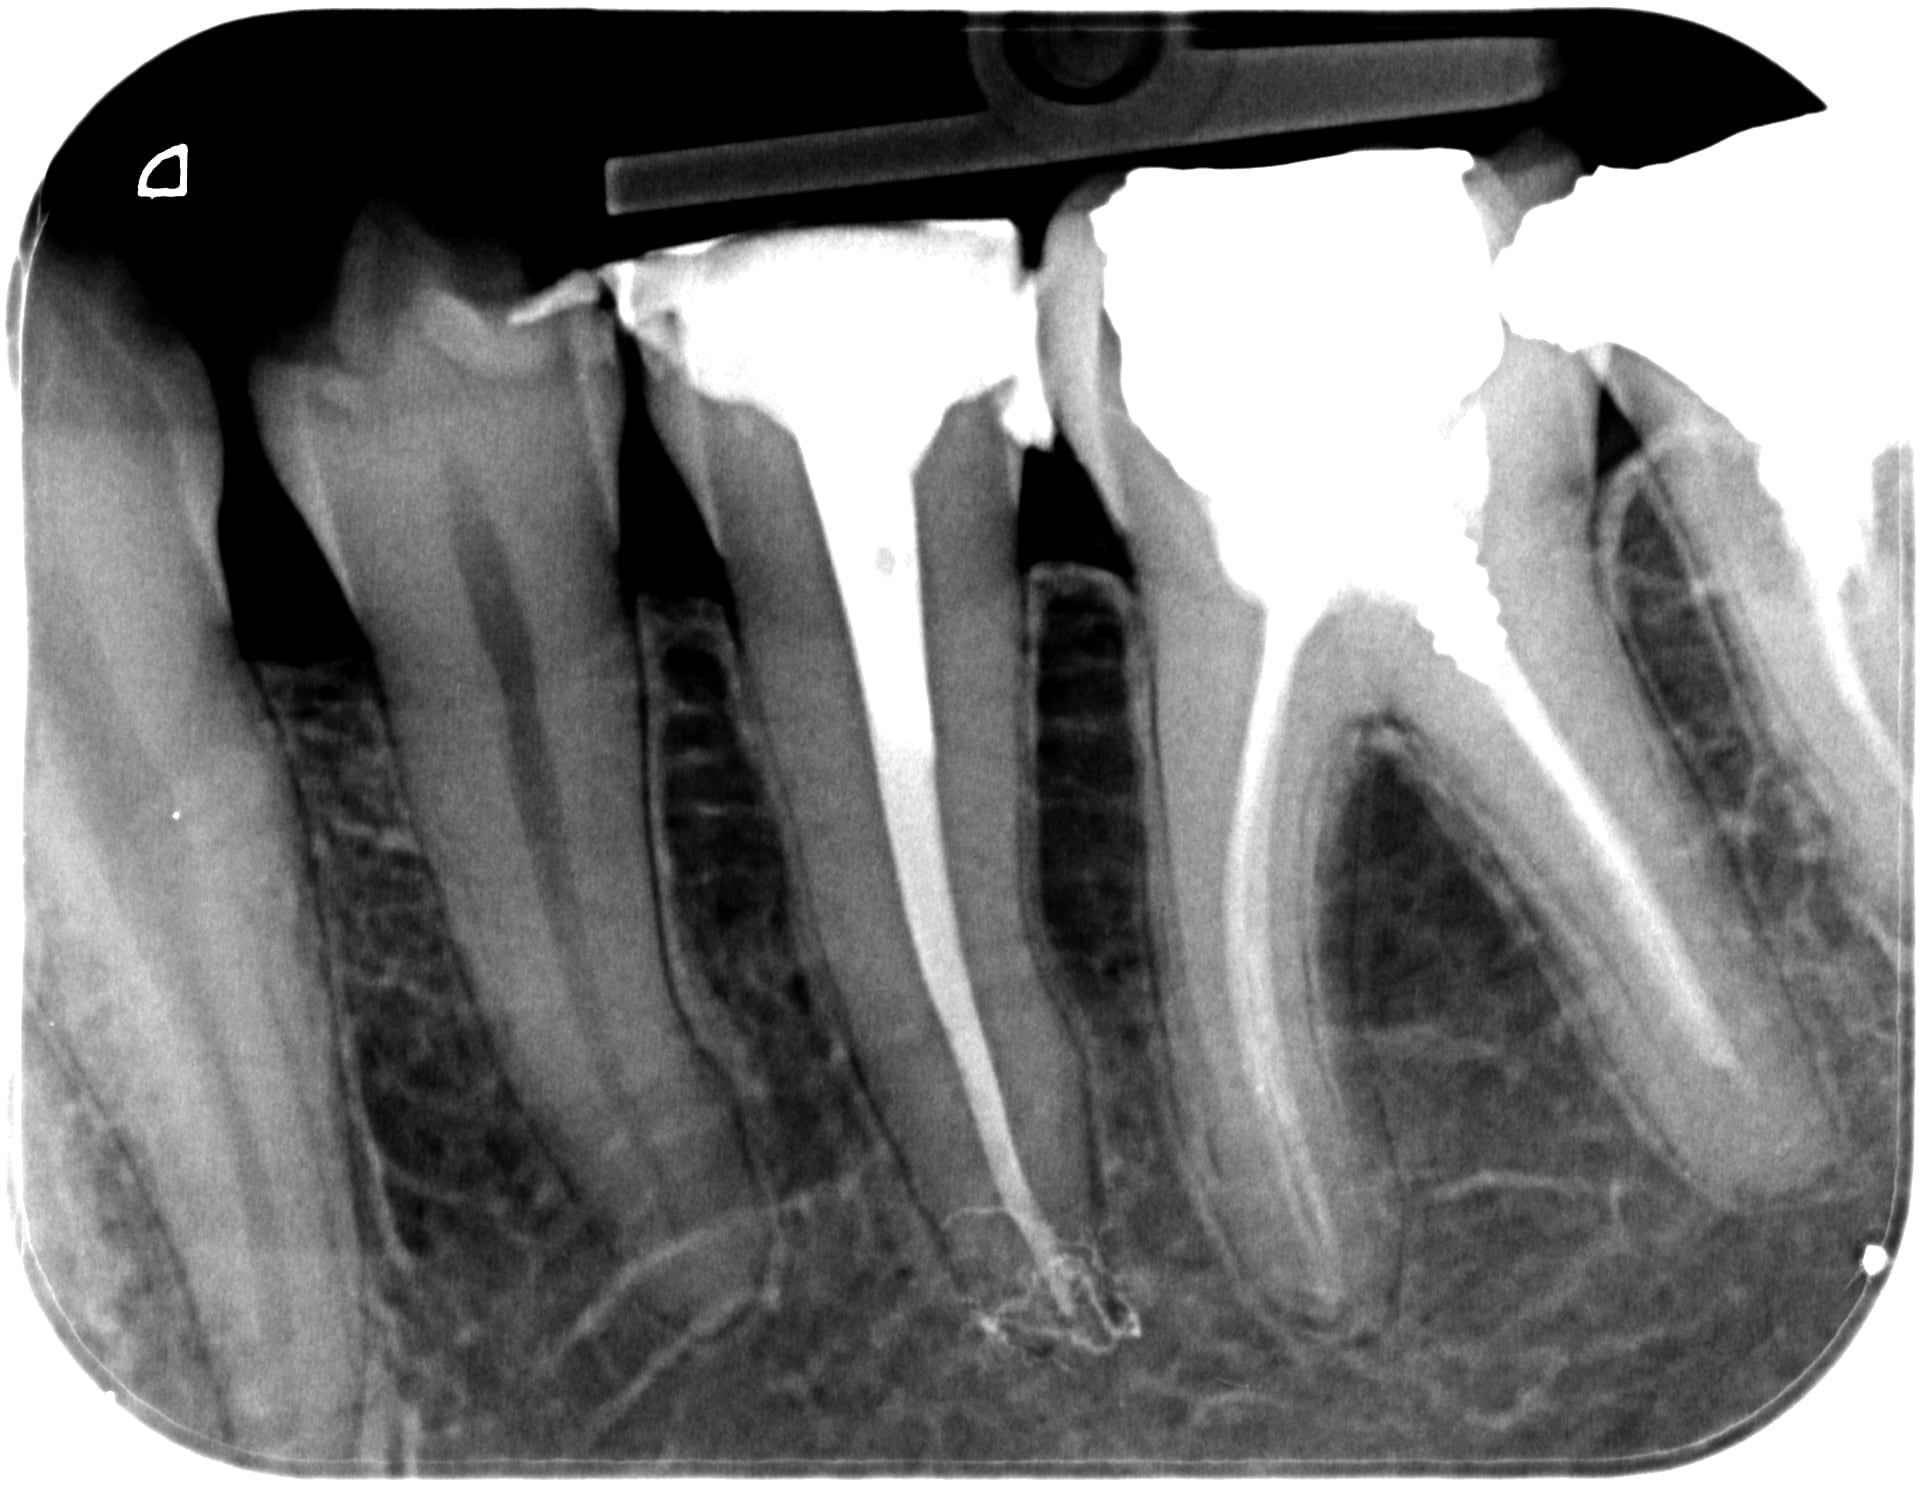

je suis passé au AH plus jet a base de résine epoxy...

bref c'est blindé de bisphénol A

Et comme on peut voir sur cette radio post op : plein de bisphénol a dans le periapex... c'est génial ! En fait, j'essaie de bien faire mais j'empoisonne mes patients.

Mais bon comme y'a pire dans les diesel et l alimentation... :)